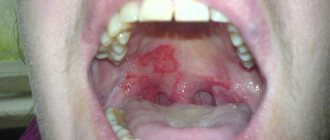

Photo: formation of ulcers with oral mucositis

Most often, this leads to the formation of ulcerative lesions of various shapes and sizes on the gums, tongue and palate.

Oral mucositis manifests itself through symptoms characteristic of this disease :

• erythema - dilation of capillaries, which indicates the presence of an inflammatory process;

• swelling of the affected area;

• necrosis of the mucous membrane, which is expressed by white spots;

• thinning of the oral mucosa;

• the formation of ulcers in several places at the same time . They can be localized on the gums, the inside of the cheeks, and the palate;

• infection of aphthae (ulcers) with subsequent discharge of pus.